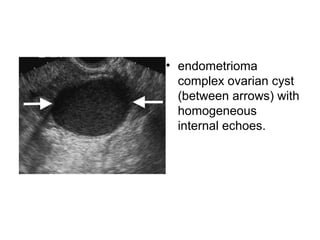

ENDOMETRIOMA

• endometrioma

complex ovarian cyst

with homogeneous

internal echoes. It

contains a small solid-

appearing area

(arrow). Color

Doppler US (not

shown) did not

demonstrate flow in

the solid area.

(between arrows) with

homogeneous

internal echoes.